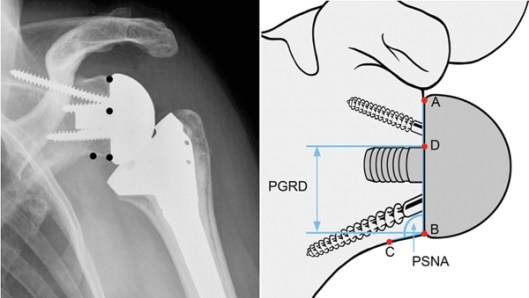

The reverse shoulder arthroplasty is a solution that directly addresses chronic deficiencies of a torn rotator cuff, compensating for its weakness or absence by rearranging the anatomy.

“In this procedure, the ball portion of the joint is taken from the humerus side and moved to the shoulder blade or scapula side and attached with an implant or prosthesis. The socket is moved to the upper end of the humerus side,” says Dr. Sabesan. “No other joint replacement surgery changes the normal anatomical structure like this.”

Like traditional shoulder replacement surgeries, the arthritic joint surfaces are replaced with a highly polished metal ball attached to a plastic socket, but in the reverse procedure, the socket and metal ball are switched. The reverse procedure constrains the ball in a cup that is inserted into the end of the humerus, and the metal ball is attached to the shoulder bone. The reversal increases tension of the deltoid muscle, producing more torque. In this way, the deltoid muscle compensates for the loss of rotator cuff by becoming the primary elevator of the shoulder joint and making it easier for a patient to raise his or her arm. Yet, range of motion remains limited.